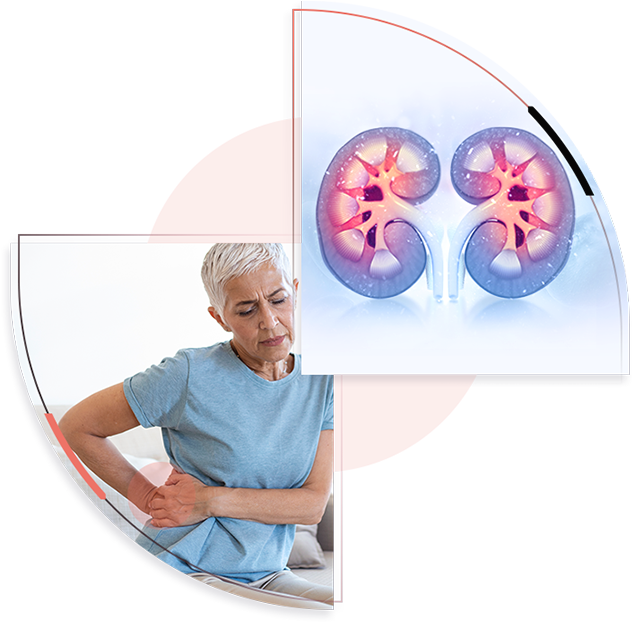

Amulya Hospital, a premier healthcare institution in Eluru, pioneered and brought to life

almost three decades back under the astounding leadership of Dr. I.C. Chenchaiah,

Orthopedic surgeon who has played a pivotal role in redefining the health care field of

Eluru. Renowned for its state-of-the-art facilities and experienced medical team, the

hospital offers a wide range of specialties including orthopedics,

gynecology, and urology.